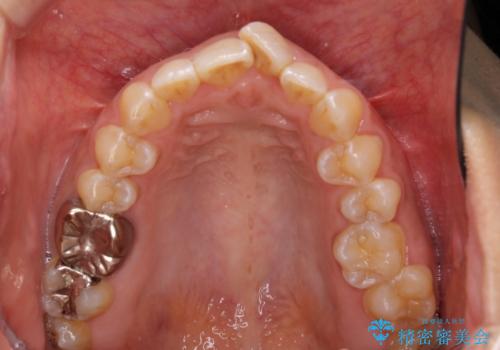

インビザラインによる狭窄歯列の拡大矯正

- 前歯のデコボコを治したいとのことで来院された患者様です。

上下顎ともに歯列全体の後方移動と側方拡大、IPR(歯と歯の間を削る)によってデコボコが解消するように設計し、インビザラインにより治療を行うこととしました。

後方移動に際し、上下の親知らずは4本とも抜歯することとしました。